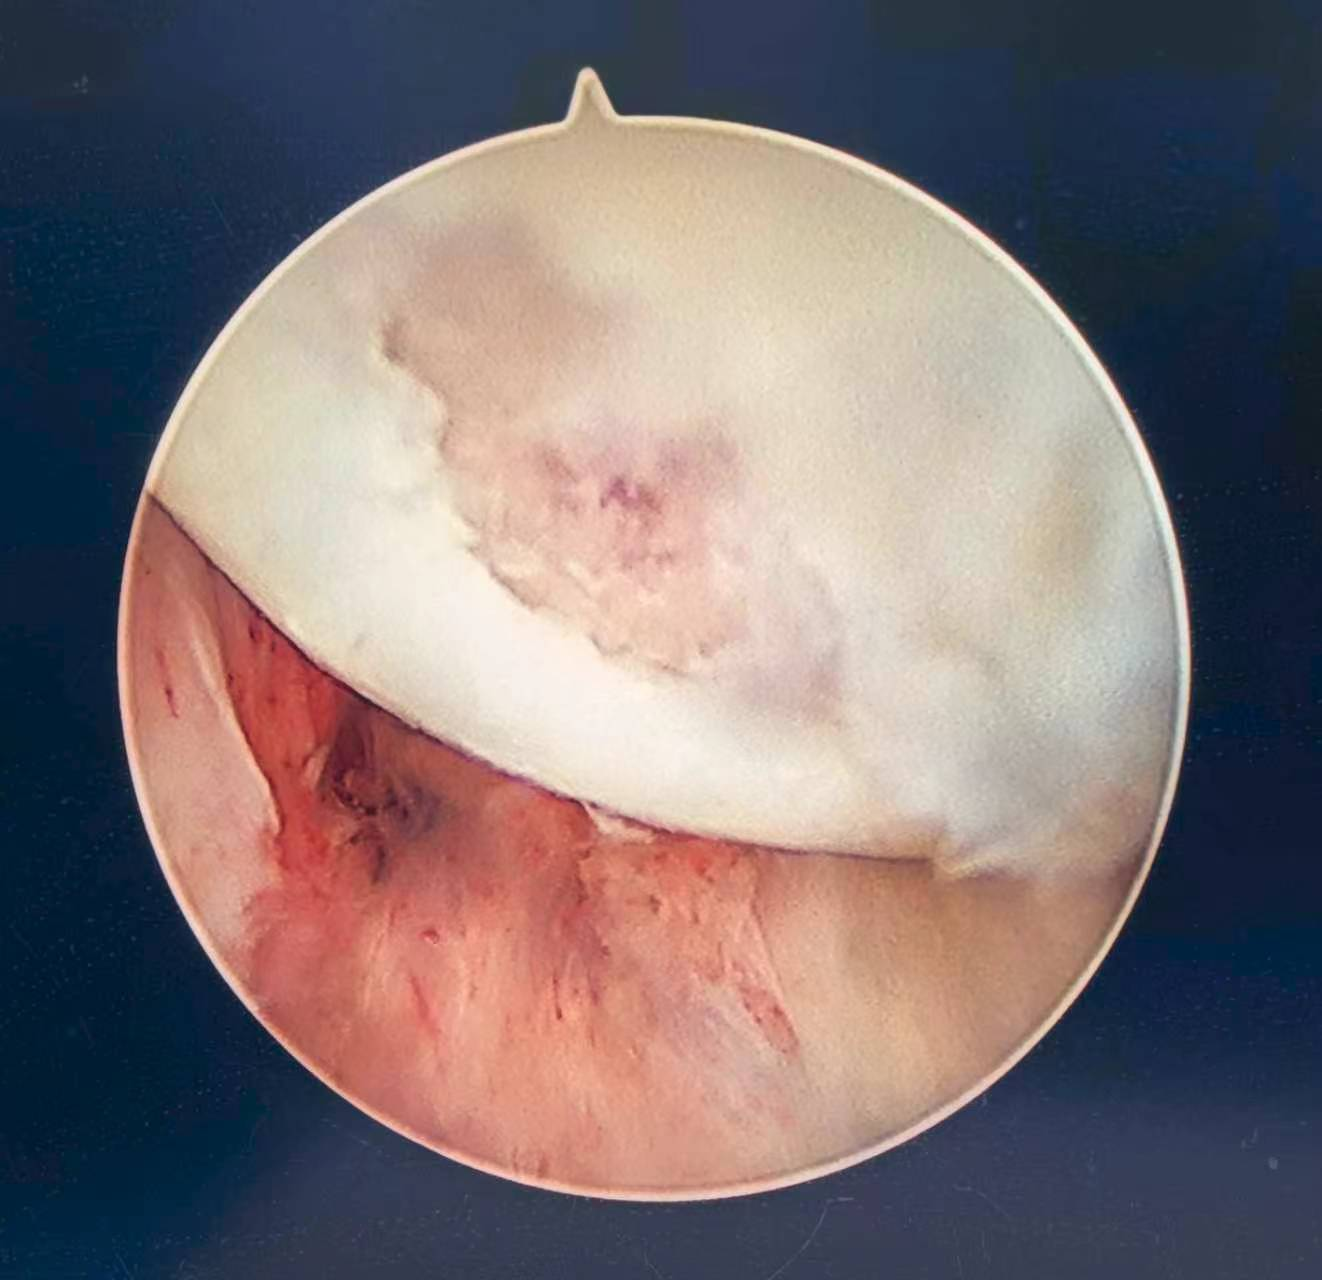

腕关节镜下可见月骨软骨剥脱,囊性改变,予以微骨折术